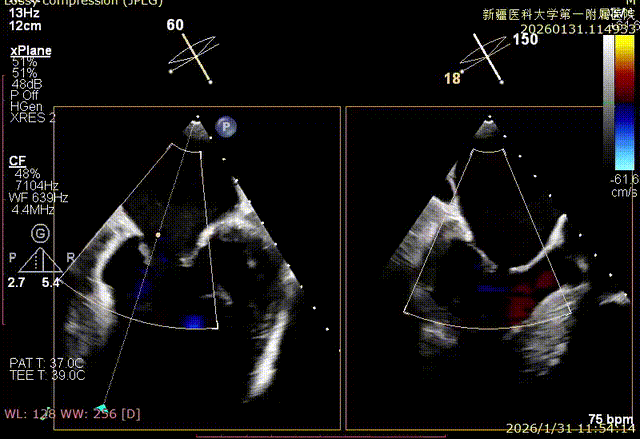

Bicom切面中重度反流

XTR弹道测试

3D enface 完成orientation调整

捕捞足够瓣叶后下Gripper,bouncing明显

缓慢关紧夹臂,同时小心多次释放张力

双孔组织桥稳定

3D enface反流充分降低

术后平均跨瓣压差1mmHg